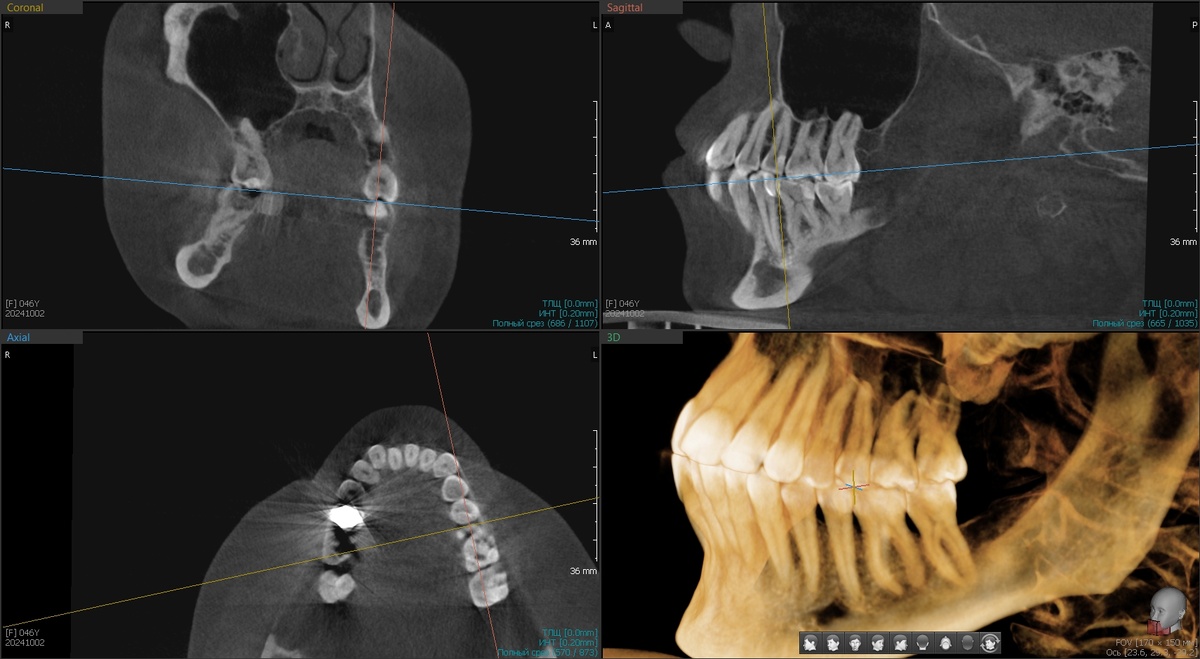

Пациентка показывает зубы:

Состояние до

Смотрю на рентген - кость в межзубных промежутках без деструкции.

-2

Её много, она плотная, полноценная. Никакого пародонтита нет, честное слово.

И это большая удача! Если бы к такой картине добавился ещё и пародонтит с разрушением кости, пациентка была бы кандидатом на удаление всех зубов с немедленной имплантацией. Но здесь повезло - всего лишь рецессии. Зубы сами не выпадут, кость их удержит.